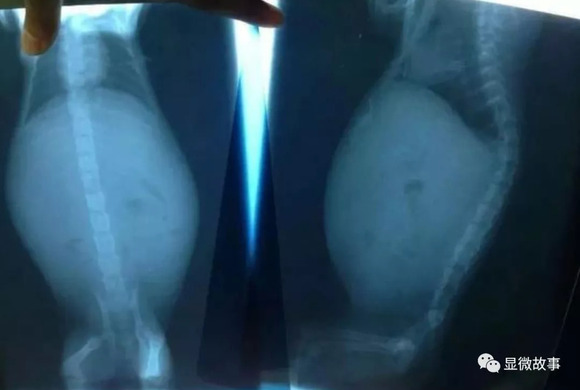

养猫的人应该都听说过猫传腹,全称猫传染性腹膜炎,这种病致死率高达95%。

直到近两年,人们才发现了两种针对猫传腹的特效药GC376以及GS-441524,简称376和441。

这两款针的费用,都在一针200元至400元之间,不同生产厂家价格有差异。

但大部分医院没有这两款药,因为没有通过我国国内的宠物药品检测,在国外也属于观察阶段。

但爱猫心切的主人肯定不能放弃这两款被证明初步有效的药,毕竟猫传腹基本等同于猫中绝症,用药不一定好,但不用药,猫一定会因为腹水导致的其他脏器衰竭致死。

可怕的是,这款药需要每天打,一个疗程在两个月左右。如果中间间断了,就需要重新按两个月的疗程开始打。

也就是说,如果你希望你的猫活下来,首先要准备好1.2万第一阶段的治疗费用。

如果治疗完,腹水没有完全消除,还需要继续开启下一个两个月的疗程。

我见过太多主人最后因为经济上的原因,不得不放弃治疗。

也见过很多主人,把家里的车都卖了,就是为了给猫续命——因为他的猫的腹水持续性复发。

这对猫来说也挺折磨的,腹水会压迫肺部,最后呼吸衰竭。

但持续打针,很多主人使用的方式不对,也让皮下长了厚厚的瘤子,打针的部位也被药水整得脱毛。

然而,所有的这些努力、时间、金钱,也只不过将患猫的存活率提高到20%左右。